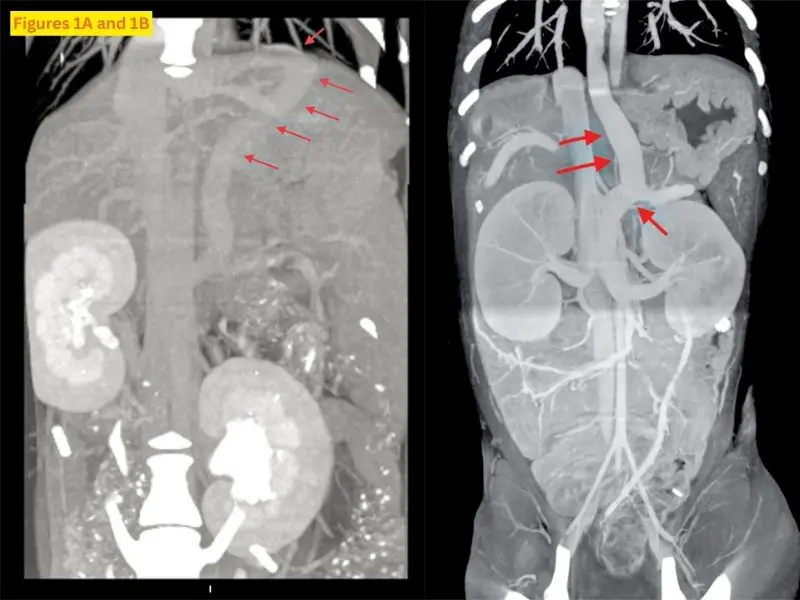

Diagnosing vascular anomalies in puppiesOctober 21, 2025There are three common kinds of vascular abnormalities in puppies that will be detailed in this article: shunts, patent ductus arteriosus (PDA), and persistent right aortic arch (PRAA).